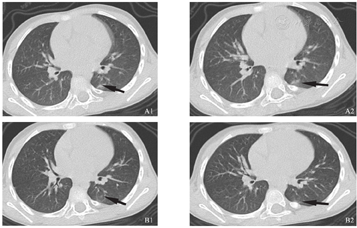

辅助检查:2月1日血常规:白细胞6.0×109/L,中性粒细胞百分比36.4%,淋巴细胞百分比42.7%,中性粒细胞计数2.18×109/L,淋巴细胞计数2.56×109/L,血红蛋白112 g/L,血小板301×109/L;C-反应蛋白0.36 mg/L;肝功能:总蛋白59.2g/L,白蛋白43.2 g/L,谷丙转氨酶58.5 U/L,谷草转氨酶83.5 U/L;心肌酶谱、肾功能、血电解质、凝血功能正常;血沉10 mm/h;胸部CT(发病当天):右肺上叶纹理增多模糊,可见条片状模糊影,考虑感染可能(图1A1、图1A2)。2月3日甲型、乙型流感病毒核酸检测阴性,呼吸道合胞病毒、腺病毒、副流感病毒抗原阴性,肺炎支原体抗体IgM阴性。2月5日(发病第5天)复查血常规:白细胞5.7×109/L,中性粒细胞百分比32.5%,淋巴细胞百分比57.5%,中性粒细胞计数1.85×109/L,淋巴细胞计数3.28×109/L;C-反应蛋白0.15 mg/L,降钙素原0.043 ng/ml。2月6日(发病第6天)胸部CT:肺部感染较前吸收(图1B1、图1B2)。2月8日(发病第8天)血常规:白细胞8.0×109/L,中性粒细胞百分比27.5%,淋巴细胞百分比65.5%,中性粒细胞计数2.19×109/L,淋巴细胞计数5.24×109/L;超敏C-反应蛋白0.06 mg/L;肝功能正常。

A1、A2:患儿发病当天,胸部CT提示右肺上叶纹理增多模糊,可见条片状模糊影;B1、B2:患儿发病第6天,胸部CT提示肺部感染较前吸收(因患儿肺部CT检查时不配合,导致图像略有模糊)。